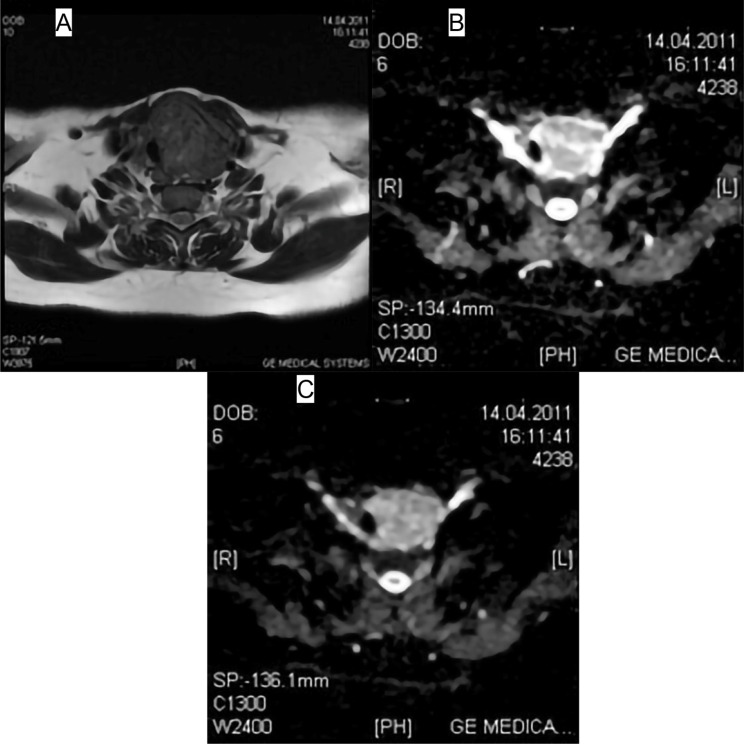

Materials and methods: Patients presenting with a preoperative diagnosis of nodular goiter or multinodular goiter were included in this study. These patients underwent neck MRI examinations, and their cases were analyzed retrospectively. A total of 26 patients were included in the study. A total of 46 nodules meeting the study criteria were examined. Measurements were performed on Apparent Diffusion Coefficient (ADC) maps of patients at two different b values (b 500 s/mm² and b 800 s/mm²), and the results were compared with histopathological findings.

Results: Out of a total of 46 nodules, 37 were identified as benign, and 9 as malignant based on histopathological analysis. The mean ADC value at b 500 was lower in malignant nodules (1259.65 ± 328.13) compared to benign nodules (19037.48 ± 472.74). Similarly, the mean ADC value at b 800 was lower in malignant nodules (1081.72 ± 200.23) compared to benign nodules (1610.44 ± 418.06). When a cut-off value of 1.1 × 10- 3 was accepted for the differentiation of pathology, the sensitivity for distinguishing pathology with ADC values at b 500 was 83.3%, with a specificity of 90.0%, and for ADC values at b 800, the sensitivity was 71.4%, with a specificity of 89.7%.

Conclusion: DW-MRI without the need for contrast agent administration is a useful method in the differentiation of benign-malignant thyroid nodules.